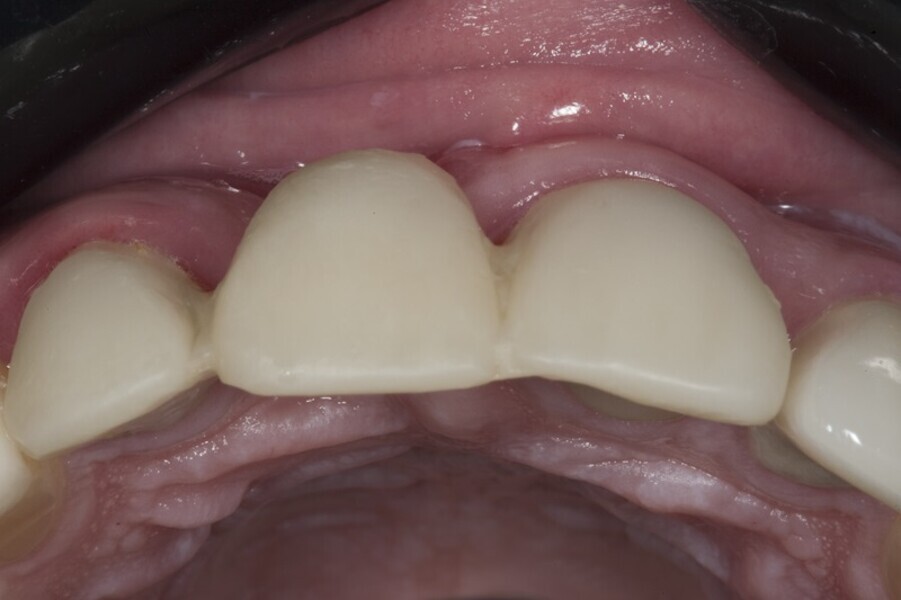

Biomodulacja laserem Nd:YAG z użyciem głowicy Genova®